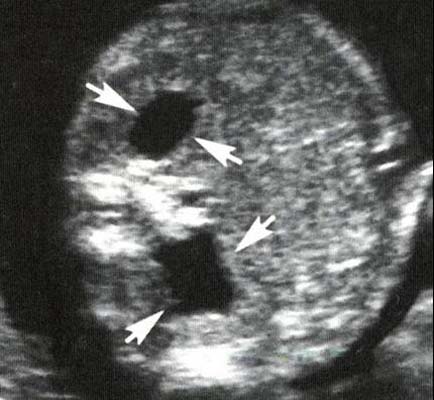

Si atteinte bilatérale ou unilatérale sur rein unique, apprécier :

- La morphologie du parenchyme rénale